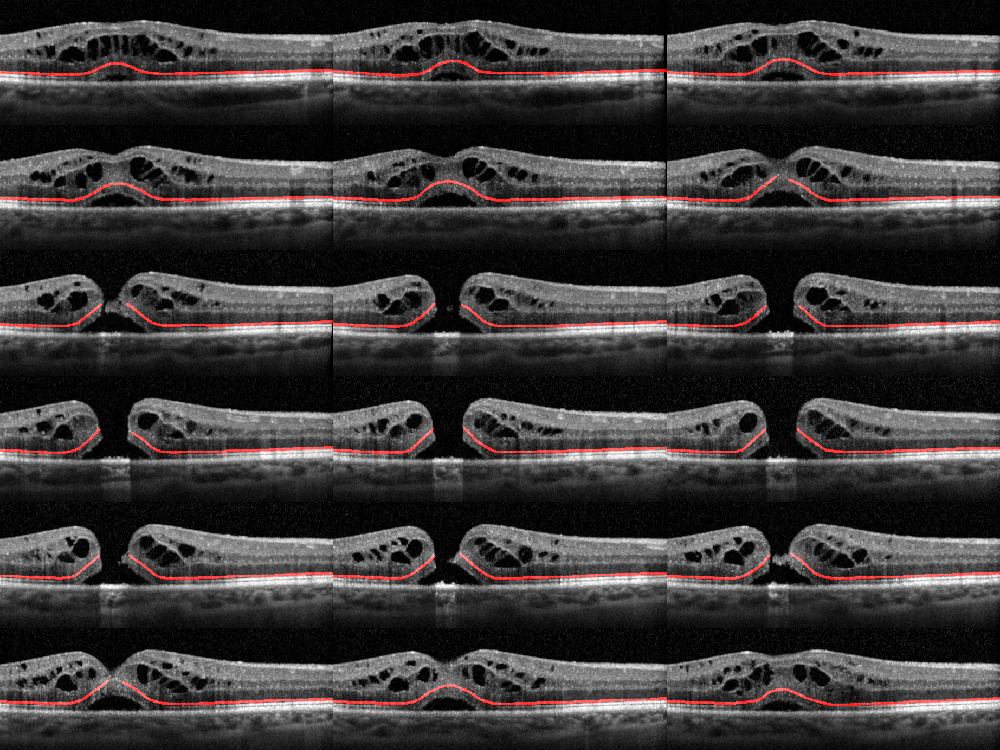

Biomedical Data Annotation: An OCT Imaging Case Study

We evaluate the quality of diabetic macular edema (DME) intraretinal fluid (IRF) biomarker image annotations on OCT B-scans from five clinicians with a range of experience. Our investigation shows a notable variance in annotation performance, with a correlation that depends on the clinician's experience with OCT image interpretation of DME.

External Limiting Membrane

We design a new benchmark for the segmentation of the retinal external limiting membrane (ELM) using an image dataset of spectral domain optical coherence tomography (OCT) scans in a patient population with idiopathic full-thickness macular holes. Then, we compared qualitative and quantitative results with seven state-of-the-art machine learning-based segmentation methods to identify the ELM line with an automated system.